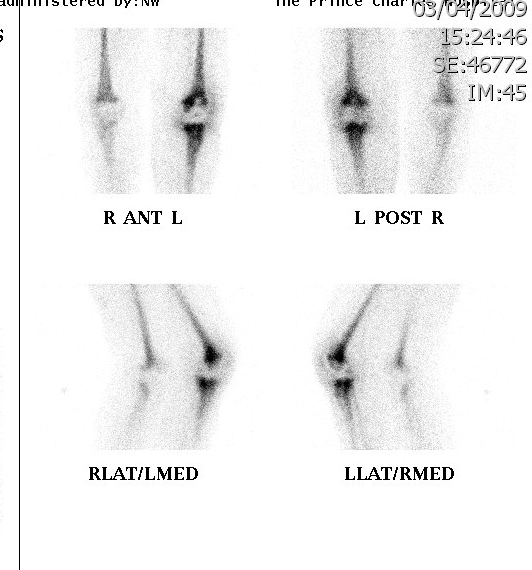

Bone Scan

Problems

- very sensitive, poor specificity

- can have increased vascularity for several months

- 1 year post cemented TKR

- 18 months post uncemented TKR

Advantage

- pathology unlikely if negative

Infection

- diffuse uptake all 3 phases (blood flow, early and delayed bone phase)

Loosening

- focal uptake unless whole prosthesis loose

- nil increase on blood flow or blood pool

Also diagnose

- stress Fractures

- RSD